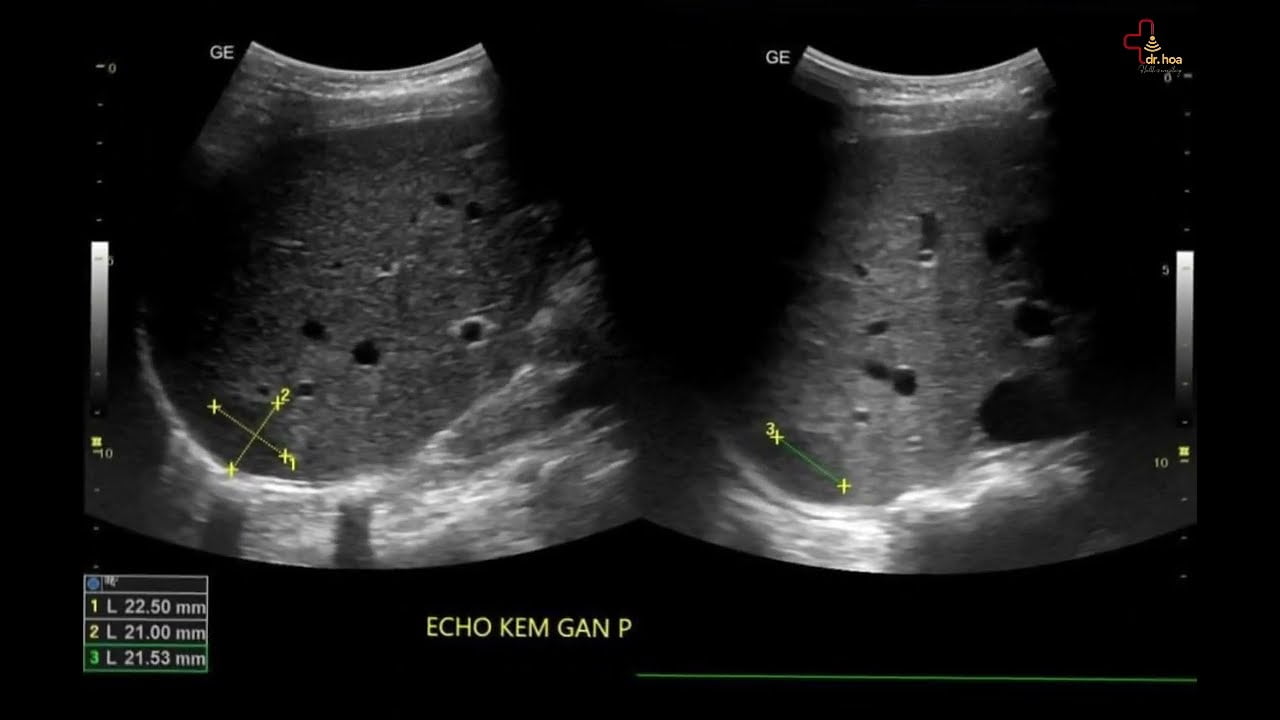

Sieu am bung tong quat kiem tra gan mat. Ket qua on a

Siêu âm bụng tổng quát kiểm tra gan, mật. Kết quả ổn ạ! #siêu_âm_bụng_tổng_quát

Sieu am Q7 xin chia se nhung hinh anh sieu am U mach mau gan. sieu am bung tong quat

Siêu âm Q7 xin chia sẻ những hình ảnh siêu âm U mạch máu gan. #siêu_âm_bụng_tổng_quát